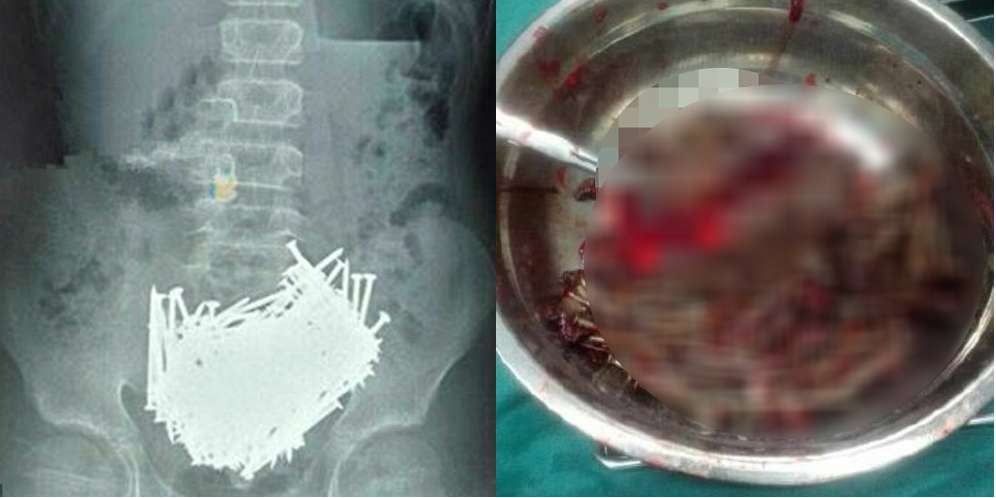

Dream - Sebanyak 200 paku ditemukan bersarang di dalam perut bocah berusia 15 tahun asal Ji'an, Provinsi Jiangxi, China. Logam-logam tersebut diduga dimakan bocah yang tak disebutkan namanya itu dalam rentang waktu sebulan.

Keberadaan paku-paku ini diketahui setelah bocah lelaki itu mengeluh sakit perut. Keluhan itu disampaikan kepada orangtuanya pada 6 Juni 2016. Mendapat keluhan itu, semula orangtuanya menganggap anaknya itu hanya sakit perut biasa.

Namun, karena tak ingin terjadi apa-apa, bocah tersebut dibawa ke rumah sakit. Dokter memeriksanya. Untuk memastikan penyakit apa yang diderita, bocah itu menjalani CT scan.

Dan betapa terkejutnya para dokter yang menangani bocah ini. Sebab, mereka melihat benda aneh di dalam perut bocah ini. Hasil CT scan menunjukkan tumpukan paku bersarang di lambung.

Operasi pun segera dilakukan. Sebanyak 200 paku berhasil dikeluarkan. Tak hanya paku, ditemukan pula tusuk gigi, batu, dan koin. Semua benda itu beratnya hampir 7 kilogram.

Setelah operasi itu sang bocah mengaku telah memakan benda-benda itu selama sebulan belakangan. Kepada wartawan, orangtua bocah ini mengaku tak tahu kenapa anaknya melakukan perbuatan tak lazim ini.

Menurut para dokter, bocah ini mengalami Pika, kelainan di mana seseorang cenderung memakan benda-benda asing seperti batu, besi, dan kaca. Kasus seperti ini bukanlah kasus pertama di dunia. (Sumber: Daily Mail)